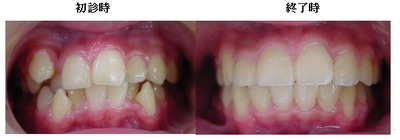

歯を抜かないと治療出来ないと言われた方に。(歯並びが悪い)

以下の上顎の症例では左右の第一小臼歯を抜かないと治療出来ないと説明があるはずです。しかし、当院での治療終了時には顎骨が拡大して綺麗に歯が並んでいます。

初診時 終了時

当院では拡大装置などを使用する事無く歯並びを綺麗に並べることが出来ます。

治療期間3年0か月で機能的で美しい咬み合わせが完成しました。

今回の症例は一般的に抜歯(第一小臼歯)が必要な症例ですが当院では非抜歯で治療する事が出来ました。